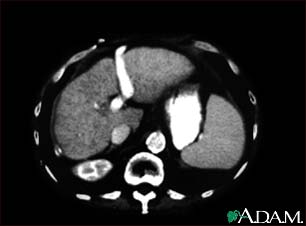

Liver cirrhosis, CT scan

A CT scan of the upper abdomen showing cirrhosis of the liver.